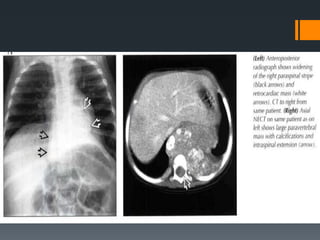

Right-sided retrosternal

goiter. (a) PAchest

radiograph demonstrates a

goiter (arrow) extending

into the middle

mediastinum, obliterating

the right paratracheal

stripe, and causing

deviation of the trachea to

the left (black arrowhead).

Above the level of the

clavicles, the margins of

the mass are not sharp

(white arrowhead),

indicating that the mass

has an anterior mediastinal

component.

Posterior mediastinal masses above the level of the clavicles have an interface with

lung and therefore typically have sharp, well-defined margins; in contrast, anterior

masses above the level of the clavicles do not have an interface with lung, so that their

margins are not usually sharp.

(b) CT scan shows the mass (arrow) between the trachea and right lung, a location

that explains the obliteration of the right paratracheal stripe seen in a. There is no

contact between the anterior component of the mass and the lung (arrowhead) at the

level of the clavicular heads, a relationship that continues above the level of the

clavicles. This finding explains why the lateral border of the anterior mediastinal

component above the level of the clavicles is not sharp in a.

Right-sided retrosternal goiter. (a)PAchest radiograph demonstrates a goiter (arrow) extending into the middle mediastinum, obliterating the right paratracheal stripe, and causing deviation of the trachea to the left (black arrowhead). Above the level of the clavicles, the margins of the mass are not sharp (white arrowhead), indicating that the mass has an anterior mediastinal component. Posterior mediastinal masses above the level of the clavicles have an interface with lung and therefore typically have sharp, well-defined margins; in contrast, anterior masses above the level of the clavicles do not have an interface with lung, so that their margins are not usually sharp.

(b) CT scanshows the mass (arrow) between the trachea and right lung, a location that explains the obliteration of the right paratracheal stripe seen in a. There is no contact between the anterior component of the mass and the lung (arrowhead) at the level of the clavicular heads, a relationship that continues above the level of the clavicles. This finding explains why the lateral border of the anterior mediastinal component above the level of the clavicles is not sharp in a.